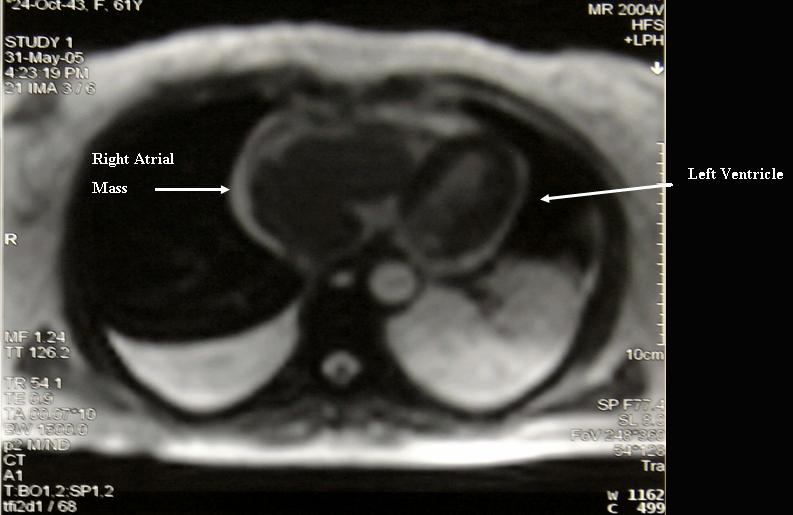

Primary right atrial lymphoma. Magnetic Resonance Imaging # Description : Magnetic Resonance Imaging of primary right atrial lymphoma